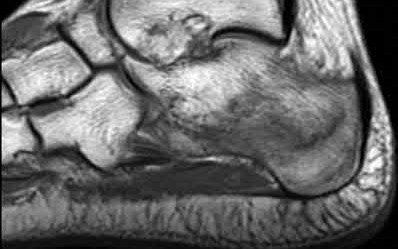

A 38-year-old male suffers the injury shown in Figure A. During operative fixation, free osteoarticular fragments are encountered and reconstruction of these pieces is attempted. Postoperatively, which of the following will have the most beneficial effect on the healing potential of the surviving chondrocytes within these reconstructed articular segments?

Figure A demonstrates a comminuted tibial plateau fracture with significant intra-articular involvement. Basic science evidence has demonstrated that post-operative gentle compressive loading may have a positive impact on articular cartilage healing; however, excessive shear loading may be detrimental.

Irrgang et al provide guidelines for rehabilitation following surgical management of articular cartilage lesions of the knee. They state that after articular cartilage repair, exercises to enhance muscle function must be done in a manner which minimizes shear loading of the joint surfaces in the area of the lesion. The authors also discuss the benefits of gentle compressive loading and motion of the joint, and its positive effects on chondrocyte nutrition.

Furthermore, they recommend a period of protected weight bearing as often being necessary, and that this should be followed by progressive loading of the joint.